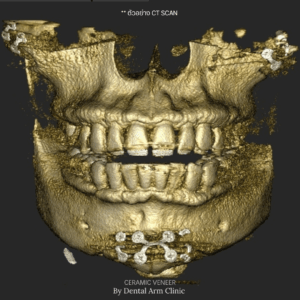

จะเห็นได้ว่าการตัดเหงือกทั้งสองแบบเหมาะกับสภาวะของเหงือกและฟันที่ไม่เหมือนกัน โดยปกติแล้วทางคลินิกจะใช้วิธีการเอ็กซเรย์แบบสามมิติ (CBCT)

เพื่อประเมินลักษณะของเหงือก ฟันและกระดูกรอบบ้าฟัน ว่าจำเป็นจะต้องตัดเหงือกแบบไหน (เป็นวิธีที่แม่นยำและไม่เจ็บตัวเลย) ทั้งนี้แนะนำว่าให้ลองเข้ามาปรึกษากับคุณหมอดูก่อนว่าควรจะทำแบบไหนดีเพื่อที่ให้ได้เหงือกที่สวยที่สุดและอยู่กับเราได้นานที่สุดนะครับ